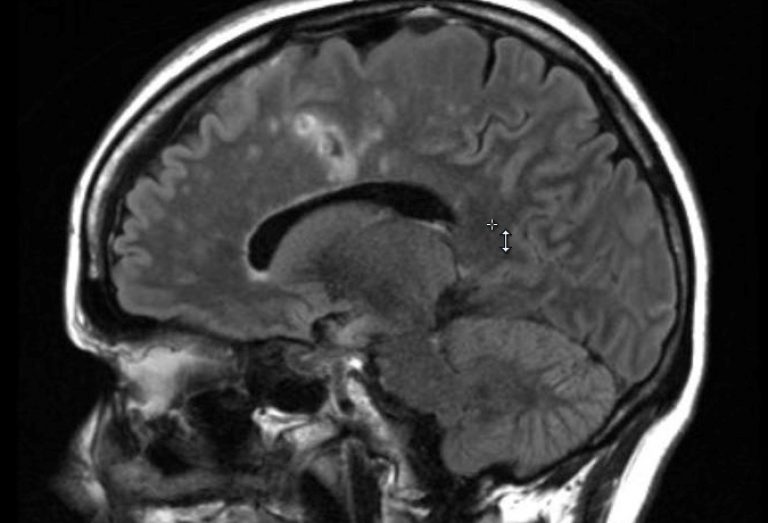

Multiple sclerosis is a neurological disease where the body’s immune system attacks myelin, the protective coating on the nerves in the brain and spinal cord. Many patients initially present with sudden, painful vision loss and can develop a wide variety and severity of symptoms based on what parts of their brain and spinal cord are impacted. The most common symptoms include fatigue, trouble walking, bowel or bladder problems, and difficulty with memory. Most cases of multiple sclerosis have no known genetic link. However, a small subset of patients has a family history of multiple sclerosis. This is called familial multiple sclerosis, and these patients tend to present with symptoms at a younger age than patients with sporadic multiple sclerosis. There are currently no cures for multiple sclerosis, so disease management is critical to help slow disease progression. We have extensive experience treating and managing familial multiple sclerosis here at UConn Health.